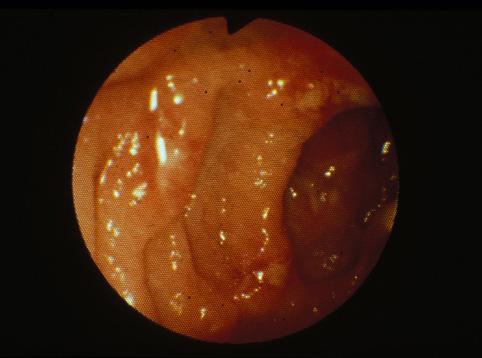

Disentería Amebiana del Colon que tuvo como lozalización principal el Ciego y el Recto

Enfermedad Inflamatoria - Ulcerativa/Disentería Amebiana

colon/ciego

Endoscopia